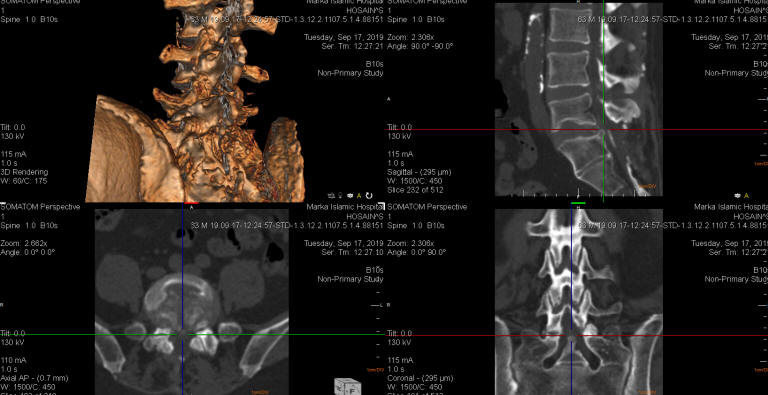

13-OCTOBER-2019  HUSSEIN ABDEL-WAHAB ABDEL-JABER  54 YEARS  SEVERE STENOSIS L4-5, L5-S1 WITH EXTRUDED DISC L5-S1.

The patient came to the clinic 03-October-2019 complaining of LBP after falling down 03-September-2019. Three days later got numbness both lower limbs with weak and pain left upper limb. Intermittent claudication. MRI lumbar spine performed 16-September-2019, bad quality, showing extruded disc L5-S1 with stenosis. CT-scan lumbar area performed 17-September-2019 showing normal facets, no overmobility and myodil contrast at the bottom of the dural sac from myelography performed 40 years ago. The patient underwent discectomy twice for extruded disc L5-S1 40 years ago. The patient has diabetes mellitus and hypertension for 30 years. Stinting 1 year ago. He has spring allergy.

The patient was sent for investigations: MRI whole spine done 05-October-2019 showed OPLL cervical spine with mild stenosis C5-6, small PDD D7-8 more to the right and severe stenosis L4-5 and L5-S1 with extruded disc L5-S1. The patient was sent to cardiac consultation and to stop anticoagulants for 7 days before surgery.

CT-scan reconstruction, showing the old surgeries with myodil in cul de sac with calcified disc L5-S1. The old approach was directed to S1-2 level.